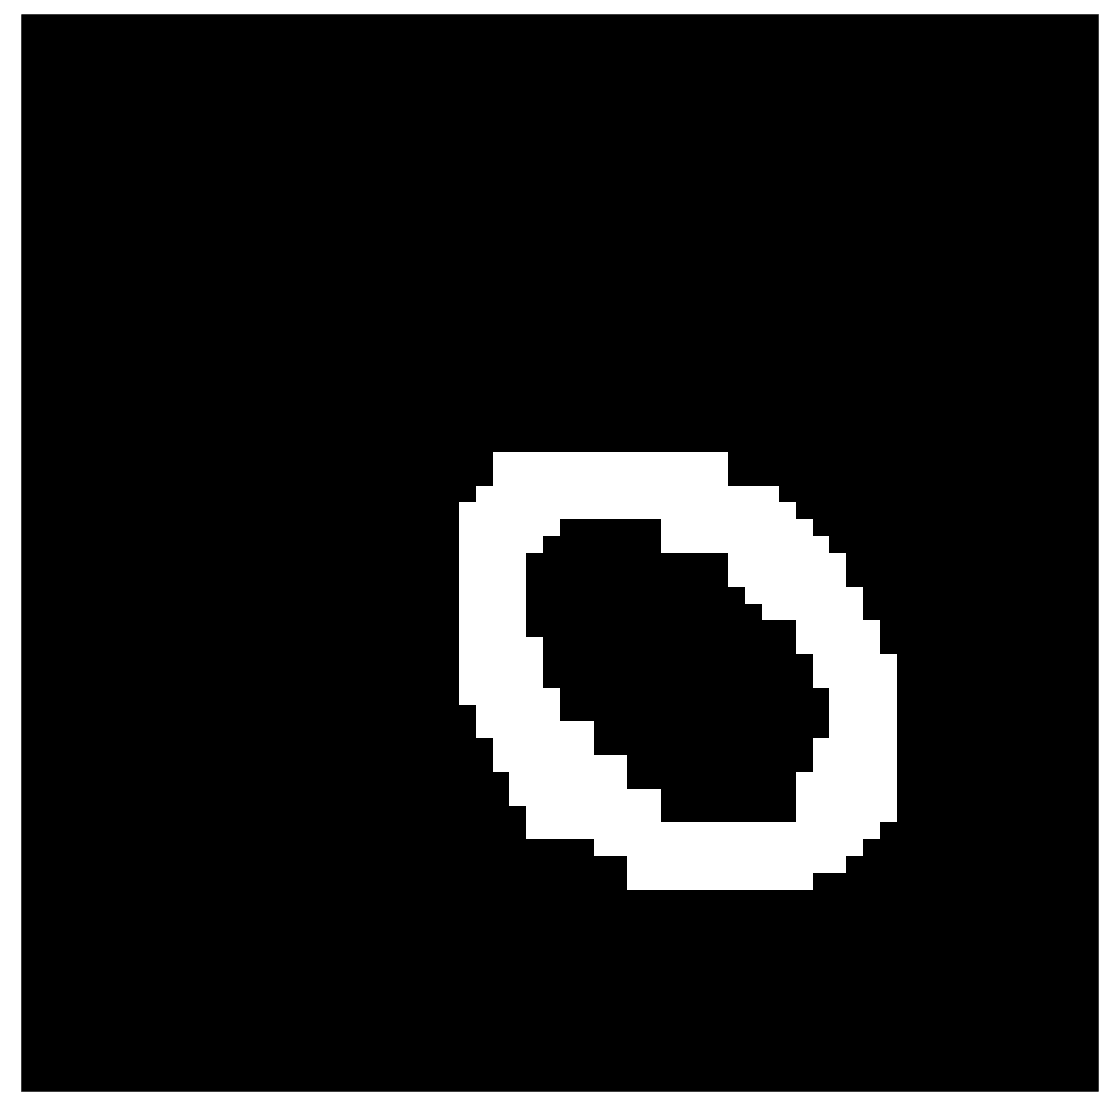

We compute the aforementioned boundary estimate in several steps, including the application of two distinct convolutional neural networks. (a) The first neural network learns to extract the known part of the wavefront set by transforming morphologically opened complex wavelet coefficients to a binary form. (b) The second neural network learns to predict the complete wavefront set from the incomplete wavefront set that has been morphologically dilated. We will discuss the second network, among with the operations related to it, in Section 4.

A demonstration can be seen in Figure 8(a).

where , defined in equation (29), is a grayscale image considered as a function . The line structuring elements are the binary images shown in Figure 9 and are considered as a function . For our limited-angle problem, we use structuring elements and , since we perform opening for subbands and . The result is illustrated in Figure 8(b).

The training of the neural network uses the morphologically opened complex wavelet coefficients and . After the network performs the thresholding, it outputs a binary mask with ones indicating the location of the wavefront set. See Figure 8(c) for an example result.

See Figure 15(a) for the full singular support.

Then, we can compute the boundary estimate of the singular support using the morphological skeleton operation described in equation (23) of section 2.4. See Figure 15(b). Finally, this learned boundary estimate can be used as an overlay for the PDFP reconstruction. See section 5 for final results.